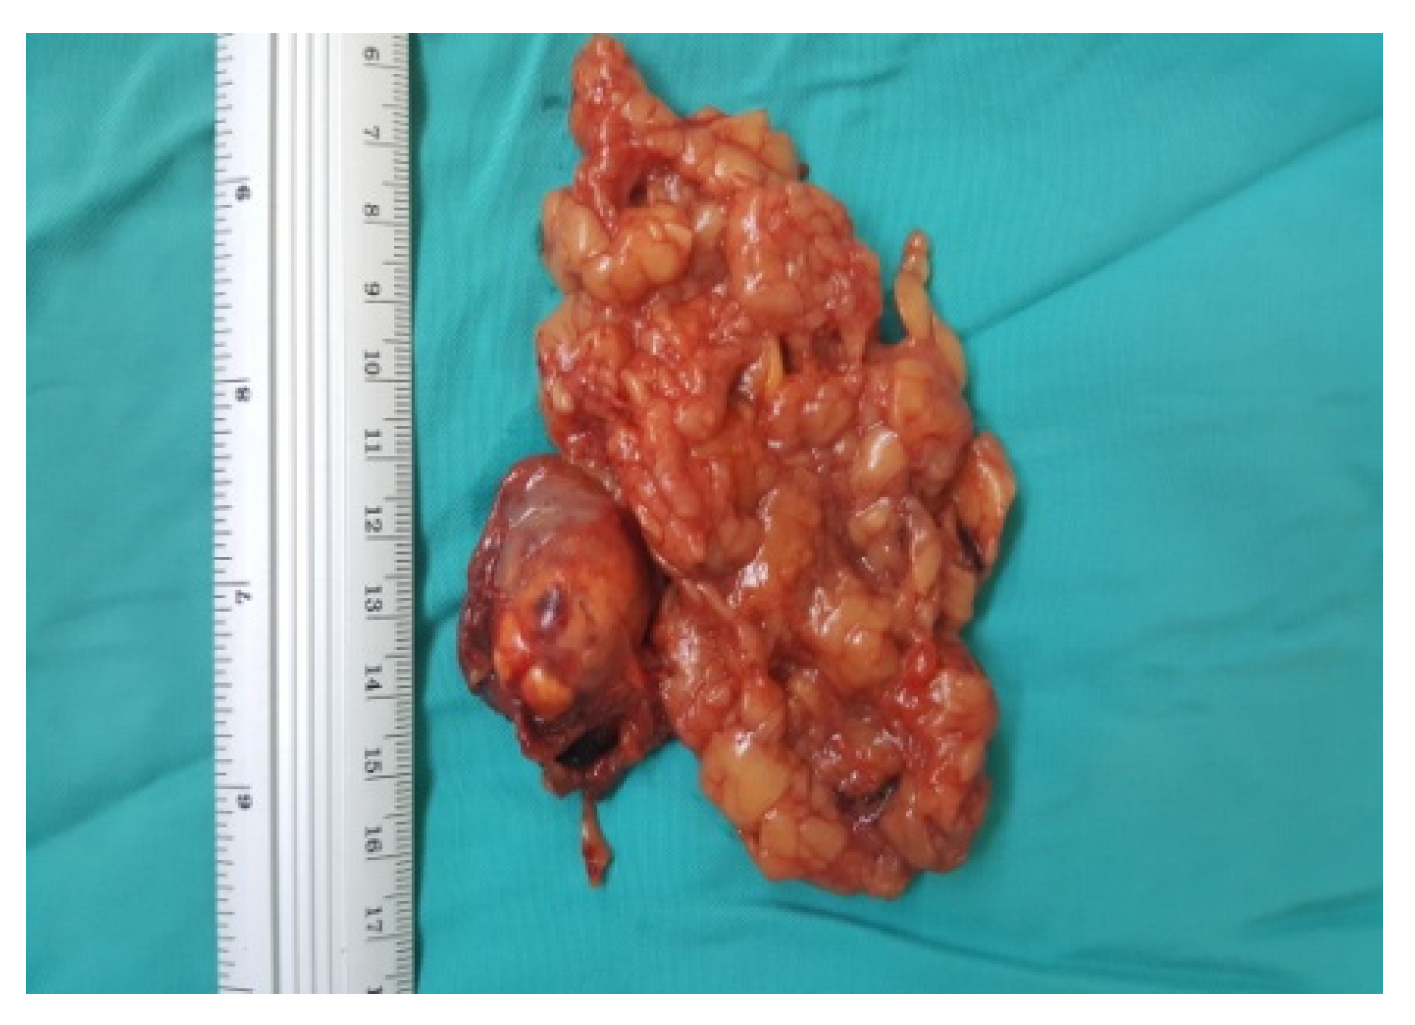

Final aspects of the surgery are depicted in Figure 6, Figure 7 and Figure 8.

Figure 8. Surgical specimen (personal collection).